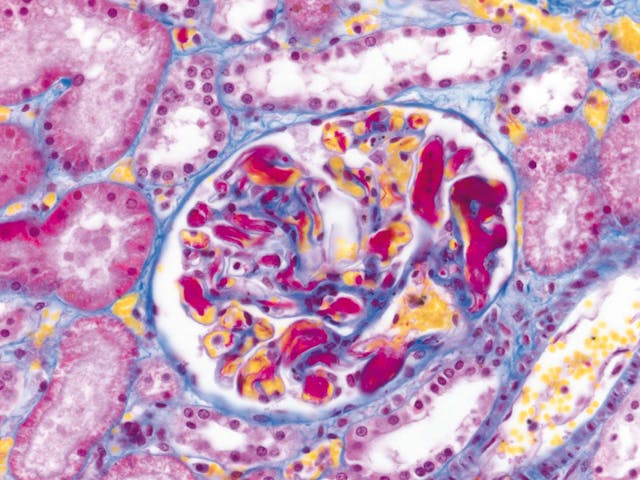

染色體標本(人) 腎組織(人)

腎組織(人) 水貂子宮內膜上皮細胞